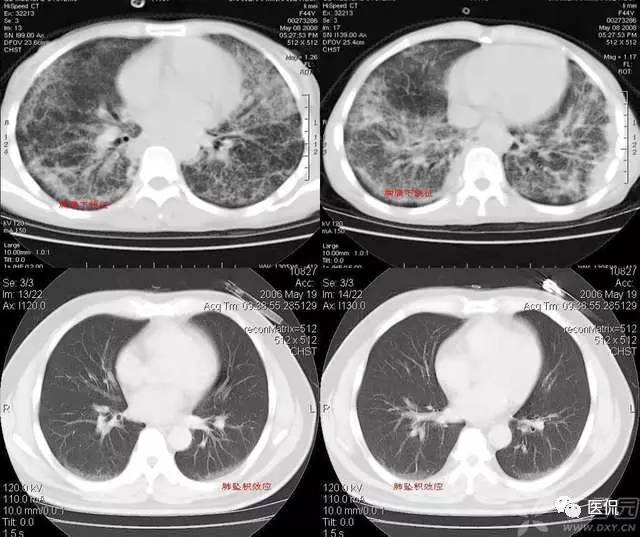

磨玻璃密度(GGO)

胸部影像上表现为肺密度的轻度增加,透过这种磨玻璃影像可以看到肺纹理的影像。该征象包括下属几种情形:1)弥漫型 如严重的急性肺移植排斥反应、早期成人呼吸窘迫综合症、肺水肿、过敏性肺炎、肺出血、各种原因的感染如非典型性肺炎等;2)斑片型 如各种类型的肺炎、肺泡蛋白沉积征、类脂质肺炎、卡氏肺囊虫病以及成人呼吸窘迫综合症等;3)局灶型 肿瘤如肺炎型肺泡癌、肺外伤、肺梗死等,这种类型常常和上述两种的病因相重叠;4)晕型 常见于早期浸袭性肺曲霉菌病,也可见于肺穿刺之后;5)支气管血管型和小叶中心型 如嗜酸性肺炎、结节病、外源性过敏性肺炎、呼吸系支气管炎等,其间前二者多见于支气管血管型,后二者多见于小叶中心型。

磨玻璃征要根据病史探求病因,如患者有出血倾向而查不出其他原因时要考虑肺出血;患者有过敏体质,又有花粉吸入或有其他过敏原接触史要考虑外源性过敏性肺炎;有多系统病变的患者要考虑结缔组织性肺炎等等。

磨玻璃影的分布对于鉴别诊断也有帮助:1)呈小叶中心分布时,一般多是早期病变,常为支气管播散,可能是过敏性肺炎或脱屑性间质性肺炎所致;2)呈全小叶分布时,病变边缘清楚;呈部分小叶受累时,病变边缘模糊。前者可见于肺泡蛋白沉积征、药物中毒性肺炎、类脂质肺炎、肺结节病、卡氏肺囊虫病、肺炎吸收期间以及肺出血等;3)呈小叶周围性分布时,多为早期特发性肺纤维化的表现。